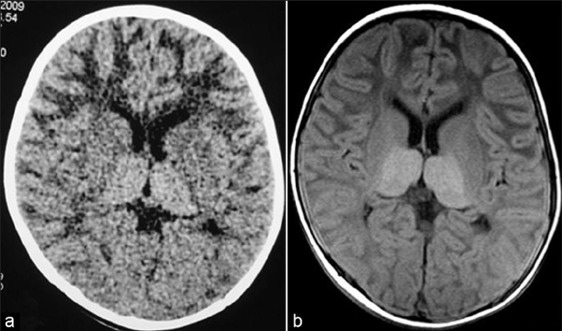

Tay-sachs disease leads to deterioration of brain matter due to beta-hexosaminidase being disrupted by the gene. Because of the disruption HEXA can no longer break down GM2 ganglioside, which builds up to toxic levels.